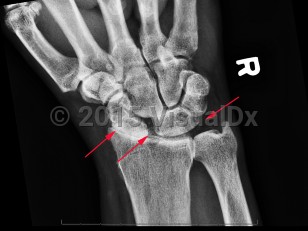

Calcium pyrophosphate deposition disease

CPPD disease usually affects patients 60 years and older and can have overlap with osteoarthritis. It affects women and men equally. Metabolic derangements such as hypophosphatemia, hypomagnesemia, and hypercalcemia increase the risk of CPPD. As such, conditions that predispose to metabolic derangements are associated with CPPD, such as hyperparathyroidism, hypothyroidism, Gitelman syndrome, hemochromatosis, and loop diuretic use. Similarly, inflammatory conditions of the joint can predispose to CPPD such as acute illness or joint trauma during the postoperative period, rheumatoid arthritis, and osteoarthritis.

The pathophysiology of pseudogout is not well understood, but CPP crystals forming in the cartilage is the first step in the disease process. Deposition of the CPP crystals affects the balance toward the production of pro-destructive prostaglandins and metalloproteinases, which destroy the chondrocytes and synoviocytes, cells that are important for the structural framework of cartilage and synovium.